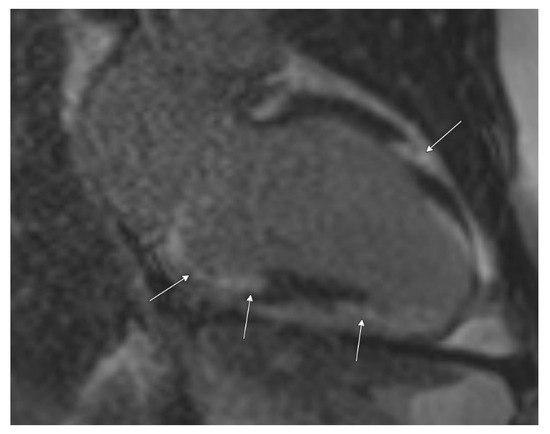

Cardiac MRI confirmed biventricular dysfunction, with left ventricular ejection fraction of 12%, right ventricular ejection fraction of 18%, basal septal akinesis/dyskinesis, and extensive abnormal late gadolinium enhancement, further supporting the suspicion of CS (Figure 3 and Figure 4). While there were no clinical signs of non-sarcoid inflammatory cardiomyopathy, a Positron Emission Tomography (PET) scan showed a very large area of diffuse myocardial FDG uptake with associated perfusion abnormalities, as described in the bull’s eye diagram, further supporting the diagnosis of CS (Figure 5). Except for cardiac abnormalities, a full-body CT PET was negative. CT coronary angiography revealed patent coronary arteries, while CT pulmonary angiography showed chronic nonocclusive segmental acute pulmonary embolus in the posterior right lower lobe without right heart strain. Ultrasonography Doppler of the lower extremities identified subacute nonocclusive superficial venous thrombosis involving the small saphenous vein, consistent with the patient’s history of KT syndrome.

Figure 3.

Cardiac MRI with late post-gadolinium-enhanced inversion recovery imaging in a two-chamber view demonstrates extensive and multifocal left ventricular myocardial late enhancement in a mid-wall and epicardial predominant distribution, particularly involving the basal inferior wall and the mid-anterior wall (arrows). Abnormal late enhancement at the apex is more diffuse in distribution.